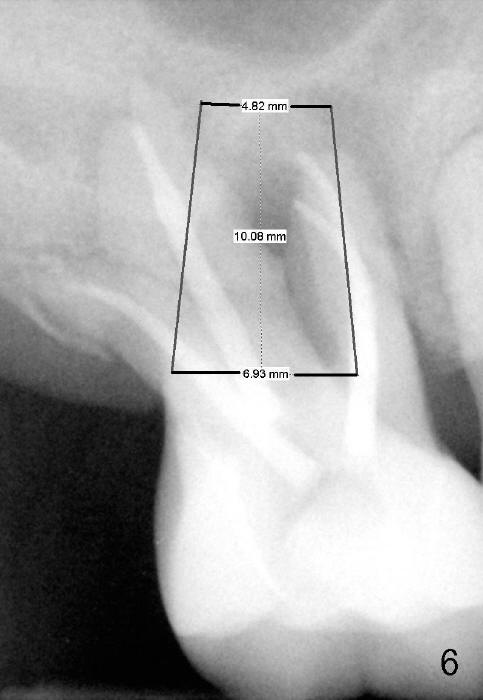

If the septum is basically intact, a 5.3x12 bone-level implant is placed in an ideal trajectory for restoration (Fig.3). The mesial and distal margin of the implant is at the level of the alveolar crests (arrows); bone graft is placed evenly to cover the coronal threads (red circles). If the septum is defective to some degree, a longer implant is placed distally (Fig.4) with more bone graft placed distally. Or the implant is placed deeper (Fig.5). If the septum is severely defective, an extra wide, but shorter implant (6.9x10 mm bone-level SM) is used (Fig.6). Or an extra wide UF implant with extra 2 mm length may offer better primary stability (Fig.6' (with sinus lift)). The primary stability of the extra wide implants is derived from contact with the mesial and distal socket walls.